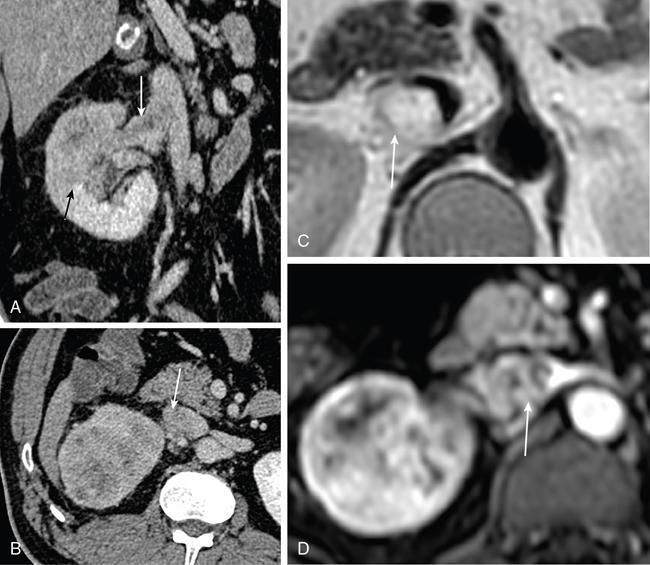

IMAGING OF RENAL MALIGNANCIES IN ADULTS Aparna Katdare, Palak Bhavesh Popat, Nilesh P. Sable, Ganesh Bakshi, Suyash Kulkarni Detection of renal masses has increased remarkably in recent times owing to wide-spread use of cross-sectional imaging. Imaging plays an important role in characterizing renal masses and is indispensable in treatment planning in renal malignancies. The most commonly encountered malignant renal masses in practice include renal cell carcinoma (RCC), urothelial carcinoma, lymphoma and metastases. Urothelial carcinoma and lymphoma have been covered in detail in separate chapters. RCC constitutes nearly 90% of all renal malignancies with a higher incidence in North America and Europe than India, Africa and China. With an increase in the number of cross-sectional studies performed, especially in Western population, the incidental diagnosis of RCC has increased in recent times, with such incidentally diagnosed lesions presenting at earlier stages with better prognosis and reduced rates of recurrence. The median age of presentation of RCC is 64 years according to the Surveillance, Epidemiology and End Results (SEER) program database and almost a decade earlier in Indian population, with a definite increasing risk of RCC with increasing age. Males are affected about 2–3.5 times more than females. In the Indian population, patients have been seen to present at a later stage as compared to the Western population. Amongst the various postulated risk factors, there is convincing evidence that smoking, hypertension, obesity and acquired renal cystic disease increase the risk of RCC. Alcohol intake and physical activity have been found to be associated with reduced risk of RCC. Trichloroethylene and cadmium exposure have been postulated as likely causes as well. Two to four per cent of RCCs are hereditary, with association of various genetic disorders such as Von Hippel Lindau (VHL) syndrome, hereditary papillary renal carcinoma, hereditary leiomyomatosis RCC, Birt-Hogg-Dube syndrome, chromosome 3 translocation and tuberous sclerosis (TCS1, TCS2). The WHO classification of 2016 (Table 11.25.1.1) stratifies tumours of the kidney into different subtypes based on cytoplasmic and architectural features, tumour location, background renal disease and molecular alterations. Clear cell renal cell carcinoma Multilocular cystic renal neoplasm of low malignant potential Papillary renal cell carcinoma Hereditary leiomyomatosis and renal cell carcinoma-associated renal cell carcinoma Chromophobe renal cell carcinoma Collecting duct carcinoma Renal medullary carcinoma MiT family translocation renal cell carcinomas Succinate dehydrogenase-deficient renal carcinoma Mucinous tubular and spindle cell carcinoma Tubulocystic renal cell carcinoma Acquired cystic disease-associated renal cell carcinoma Clear cell papillary renal cell carcinoma Renal cell carcinoma, unclassified Papillary adenoma Oncocytoma 8310/3 8316/1a 8260/3 8311/3* 8317/3 8319/3 8510/3a 8311/3a 8311/3 8480/3a 8316/3a 8316/3 8323/1 8312/3 8260/0 8290/0 Metanephric adenoma Metanephric adenofibroma Metanephric stromal tumour 8325/0 9013/0 8935/1 Nephrogenic rests Nephroblastoma Cystic partially differentiated nephroblastoma Paediatric cystic nephroma 8960/3 8959/1 8959/0 Clear cell sarcoma Rhabdoid tumour Congenital mesoblastic nephroma Ossifying renal tumour of infancy 8964/3 8963/3 8960/1 8967/0 Leiomyosarcoma Angiosarcoma Rhabdomyosarcoma Osteosarcoma Synovial sarcoma Ewing sarcoma Angiomyolipoma Epithelioid angiomyolipoma Leiomyoma Haemangioma Lymphangioma Haemangioblastoma Juxtaglomerular cell tumour Renomedullary interstitial cell tumour Schwannoma Solitary fibrous tumour 8890/3 9120/3 8900/3 9180/3 9040/3 9364/3 8860/0 8860/1a 8890/0 9120/0 9170/0 9161/1 8361/0 8966/0 9560/0 8815/1 Cystic nephroma Mixed epithelial and stromal tumour 8959/0 8959/0 Well-differentiated neuroendocrine tumour Large cell neuroendocrine carcinoma Small cell neuroendocrine carcinoma Phaeochromocytoma 8240/3 8013/3 8041/3 8700/0 Renal haematopoietic neoplasms Germ cell tumours The morphology codes are from the International Classification of Diseases for Oncology (ICD-O) {917A}, Behaviour is coded/0 for benign tumours; /1 for unspecified, borderline or uncertain behaviour; /2 for carcinoma in situ and grade III intraepithelial neoplasia; and /3 for malignant tumours. The classification is modified from the previous WHO classification (756A), taking into account changes in our understanding of these lesions. aNew code approved by the IARC/WHO Committee for ICD-O. Of these, the most common entity is the clear cell subtype, while papillary and chromophobe subtypes are less common. The different subtypes show varied biological behaviour, treatment response and prognosis. The 2017 guidelines by American Urological Association (AUA) as well as 2019 guidelines by European Society of Medical Oncology (ESMO) recommend multiphase cross-sectional imaging by either CT or MRI for renal mass characterization and staging. AUA 2017 guidelines recommend renal mass characterization on the basis of tumour complexity, contrast enhancement and presence or absence of fat. MRI has an upper hand over CT in characterizing subtle mass enhancement, cystic lesions and lesions less than 2 cm. ESMO recommends contrast-enhanced CT study of the chest, abdomen and pelvis for renal mass staging. Bone scan and brain CT or MRI can be considered if indicated by clinical or laboratory investigations. For characterization of renal masses, a multiphase CT or MRI study is recommended. CT study constitutes an unenhanced study followed by contrast injection and acquisition of corticomedullary phase at 40 seconds, nephrographic phase at around 100 seconds and delayed phase at around 5 minutes. MRI protocol includes T2-weighted single-shot fast spin-echo 2D sequences, axial T1-weighted 2D sequence with in-phase and opposed-phase gradient echo imaging, precontrast and postcontrast imaging with a 3D T1-weighted spoiled gradient recalled sequences in corticomedullary phase at 30 seconds, nephrographic phase at 100 seconds, 180–210 seconds and delayed phase imaging at 5 minutes and diffusion-weighted imaging with multiple b-values 0–50, 400–500 and 800–1000 s/mm2. The ACR White Paper on CT imaging of incidental renal mass recommends using the following descriptors for characterizing renal masses: Given the prognostic implications, it is worthwhile for radiologists to know the imaging features that may help discriminate between the common histological subtypes of RCC on various imaging modalities. This is the most common histological type of RCC, accounting for about 70% of cases. These are exophytic tumours with a heterogeneous appearance due to the presence of necrosis, intratumoural haemorrhage, cystic components with septations and calcific foci and hence have a more heterogeneous appearance on cross-sectional imaging than the other subtypes (Fig. 11.25.1.1). Necrosis is seen more often in larger masses and higher tumour grades (Fig. 11.25.1.2). On CT, depending on the tumour composition, these are seen as heterogeneous lesions, show marked contrast enhancement in the corticomedullary phase with washout on nephrogenic phase (Fig. 11.25.1.2). On MRI, these characteristically show high signal intensity on T2W sequences (Fig. 11.25.1.3). The presence of intracytoplasmic fat in the clear cells of the tumour is reflected in the loss of signal in opposed phase images on chemical shift imaging, which is seen in nearly 60% of these tumours. A pseudocapsule may be seen, which is best appreciated on T2-weighted imaging on MRI; the presence of a pseudocapsule has a high negative predictive value for perinephric extension (Figs. 11.25.1.3 and 11.25.1.4). Conversely, larger tumours with higher grades often have interrupted pseudocapsule and hence tend to be irregular, spread into the perinephric fat with renal vein and inferior vena cava (IVC) invasion (Figs. 11.25.1.5 and 11.25.1.6). On diffusion-weighted imaging, clear cell RCCs have been seen to have higher ADC values than nonclear cell RCCs, and lower-grade tumours have been seen to have higher ADC values than higher-grade tumours. The clear cell variant has worse prognosis than the papillary and chromophobe subtypes, presenting at a more advanced stage and being more likely to recur or metastasize (Fig. 11.25.1.7), with lower 5-year survival rates at 44%–69% as compared to 78%–92% for the other two. Papillary RCC comprises about 10%–15% of RCCs. These are slow-growing tumours and hence are well-marginated in contrast to clear cell RCC. As they are hypovascular, their enhancement on CT is significantly less than clear cell RCC (Fig. 11.25.1.8). These show characteristically low signal on T2W images on MRI (Fig. 11.25.1.9). Intracytoplasmic or macroscopic fat is less often seen on MRI imaging as compared to the clear cell variants. Larger tumours tend to be more heterogeneous (Fig. 11.25.1.10). These tumours may sometimes show cystic appearances, mural projections or blood degradation products. Calcifications are more common in papillary variants than clear cell RCC. Multifocality and bilaterality are also more common in these tumours than clear cell variants. These account for about 5% of RCCs. These are less aggressive, more homogeneous and hypovascular lesions than clear cell variants, with intensity of contrast enhancement on cross-sectional imaging being midway between clear cell and papillary variants. They show low to intermediate T2 signals on MRI. A characteristic feature is the presence of a central scar and spoke-wheel enhancement, the latter being a histopathological and imaging similarity between these tumours and oncocytoma (Fig. 11.25.1.11). Other subtypes of RCC are much less common but some may show distinct imaging findings. Multilocular cystic RCCs have excellent prognosis and lack mural nodules within the cystic components, unlike clear cell RCCs with cystic degeneration which show mural nodules. Collecting duct carcinomas, on the other hand, are aggressive tumours with poor prognosis and have medullary origin, and therefore appear similar to transitional cell carcinomas on imaging. Medullary RCCs are associated with sickle cell disease and sickle cell trait and are seen as infiltrating intracalyceal obstructive lesions with associated nodal disease. The imaging work-up of a suspected RCC is aimed at: Localized renal cancer is defined as a disease confined to the renal capsule and refers mainly to stage I and II disease. Nearly 70% of RCCs, especially the lower-stage lesions, are incidentally diagnosed on cross-sectional imaging. Also, amongst incidentally diagnosed renal lesions less than 4 cm in size, about 20% turn out to be benign on histopathology. Asymptomatic incidentally diagnosed small renal masses have an indolent course and better prognosis. Nephron-sparing surgery (NSS) has gathered momentum in recent years due to promising results and prognoses in small lesions. The 2017 AUA guidelines for localized renal masses describe restricted and well-defined indications for radical nephrectomy, bigger role of nephron-sparing procedures such as partial nephrectomy, tumour enucleation and thermal ablation, as well as increasing role for biopsy as well as active surveillance of such lesions. Hence, imaging findings in these lesions become critical in charting management of these patients. The imaging features of common histopathological subtypes of RCCs have already been discussed above. Signal intensity on T2W images and corticomedullary phase enhancement have been seen to be independent predictors of clear cell and papillary RCCs. Further, T2 signal homogeneity can be a predictor for slower growth rate. Hence, in general, multiparametric MRI studies have been shown to be effective in small renal mass characterization and can subsequently guide decisions regarding biopsy, surgery or surveillance. CT is a good alternative in patients with contraindication to MRI. For cystic renal lesions, the Bosniak classification, which stratifies the risk of neoplasia in cystic renal lesions based on the complexity of their appearance (wall thickness, septations, solid component), can be used effectively to decide further course of management. The Bosniak classification originally applies to CT findings but can logically be extrapolated to MRI, USG and Contrast Enhanced Ultrasound (CEUS) as well. Bosniak I and II cysts are benign while Bosniak IIF, III and IV cysts show progressively increasing risk of neoplasia. Given the more indolent course of cystic RCCs as compared to solid lesions and possible complications of interventions, lately there has been a case for even the type III and IV cysts, which previously would be operated, to be followed up, especially if patient has existing comorbidities or if the solid component is minimal. Initial follow-up would be at 6 months, followed by annual imaging. AUA 2017 guidelines recommend considering renal mass biopsy if haematologic, metastatic, inflammatory or infectious aetiology is suspected. Once the need for surgery is established in a localized disease, NSS may be considered for stage Ia and Ib disease. To predict perioperative outcomes in NSS, various scoring systems have been proposed for preoperative renal mass evaluation, such as R.E.N.A.L. nephrometry score, PADUA score (Preoperative aspects and dimensions used for anatomical classification), C-index method and mathematical tumour contact surface area (CSA). The popular R.E.N.A.L. nephrometry score takes into account various tumour descriptors that help decide the technical feasibility of NSS and predict surgical outcomes. These include tumour radius, exo/endophytic location, nearness to collecting system or renal sinus, anterior/posterior location and location with reference to polar lines. These descriptors need to be commented upon diligently while reporting renal masses (Table 11.25.1.4). Higher scores are seen to correlate with ischaemia time, postoperative urologic complications, higher grade and mortality. These include organ-confined tumours more than 7 cm in size, or tumours of any size which show regional nodal involvement and/or invasion of perinephric tissues but confined to Gerota’s fascia. These include renal vein and IVC invasion (luminal and mural). Generally, radical nephrectomy is recommended by the National Comprehensive Cancer Network (NCCN) in stage II and III RCCs. Both CT and MRI are effective in diagnosing locally advanced disease in RCC. The loss or interruption of pseudocapsule is seen in more infiltrative and aggressive disease and is best seen on MRI. Local infiltration may be in the form of contiguous spread to perinephric tissues or discrete deposits in perinephric fat (Fig. 11.25.1.15). IVC or renal vein invasion could be in the form of intraluminal thrombosis or invasion of the vessel wall and have implications on surgical approach and outcomes. Tumour thrombus can be distinguished from bland thrombus by confirming vascularity within the thrombus on imaging. Doppler evaluation, CEUS, CT and MRI can all be helpful for the same. MRI is better than other modalities for venous evaluation, especially for mural invasion and IVC invasion (Figs. 11.25.1.16 and 11.25.1.17). Right-sided tumours, anteroposterior IVC diameter of 2.4 cm or more at the level of renal hilum and complete IVC occlusion at this level are associated with higher risk of IVC resection. About 16% of patients with RCC have metastases at diagnosis and about 20%–30% of patients operated for local disease develop recurrence or metastases at a later date. The recurrent disease occurs most commonly within 3 years of diagnosis and uncommonly even later in young patients or large tumours. The most common sites of metastases from RCC are lungs, liver, bones, nodes, adrenals and brain. CT scan is the preferred modality for primary staging and surveillance for metastases because of its widespread availability and versatility for diagnosing bone and soft tissue lesions. MRI is preferred for looking for recurrence in postablative lesions, wherein these are seen as new enhancing lesions or show increase in the size of preexisting enhancing components. 18FFluorodeoxyglucose – Positron Emission Tomography (PET)/CT and PET/MRI may be helpful to look for metastatic disease as well. 18FSodium fluoride – PET/CT has been found to be better than CT and bone scan in detecting osseous metastases. RCC is a relatively radiation-resistant tumour, and treatment options tilt in favour of surgical procedures for localized and locally advanced diseases. For metastatic disease, post-risk assignment, the treatment has to be planned. Treatment can be offered as per size and the clinical stage.